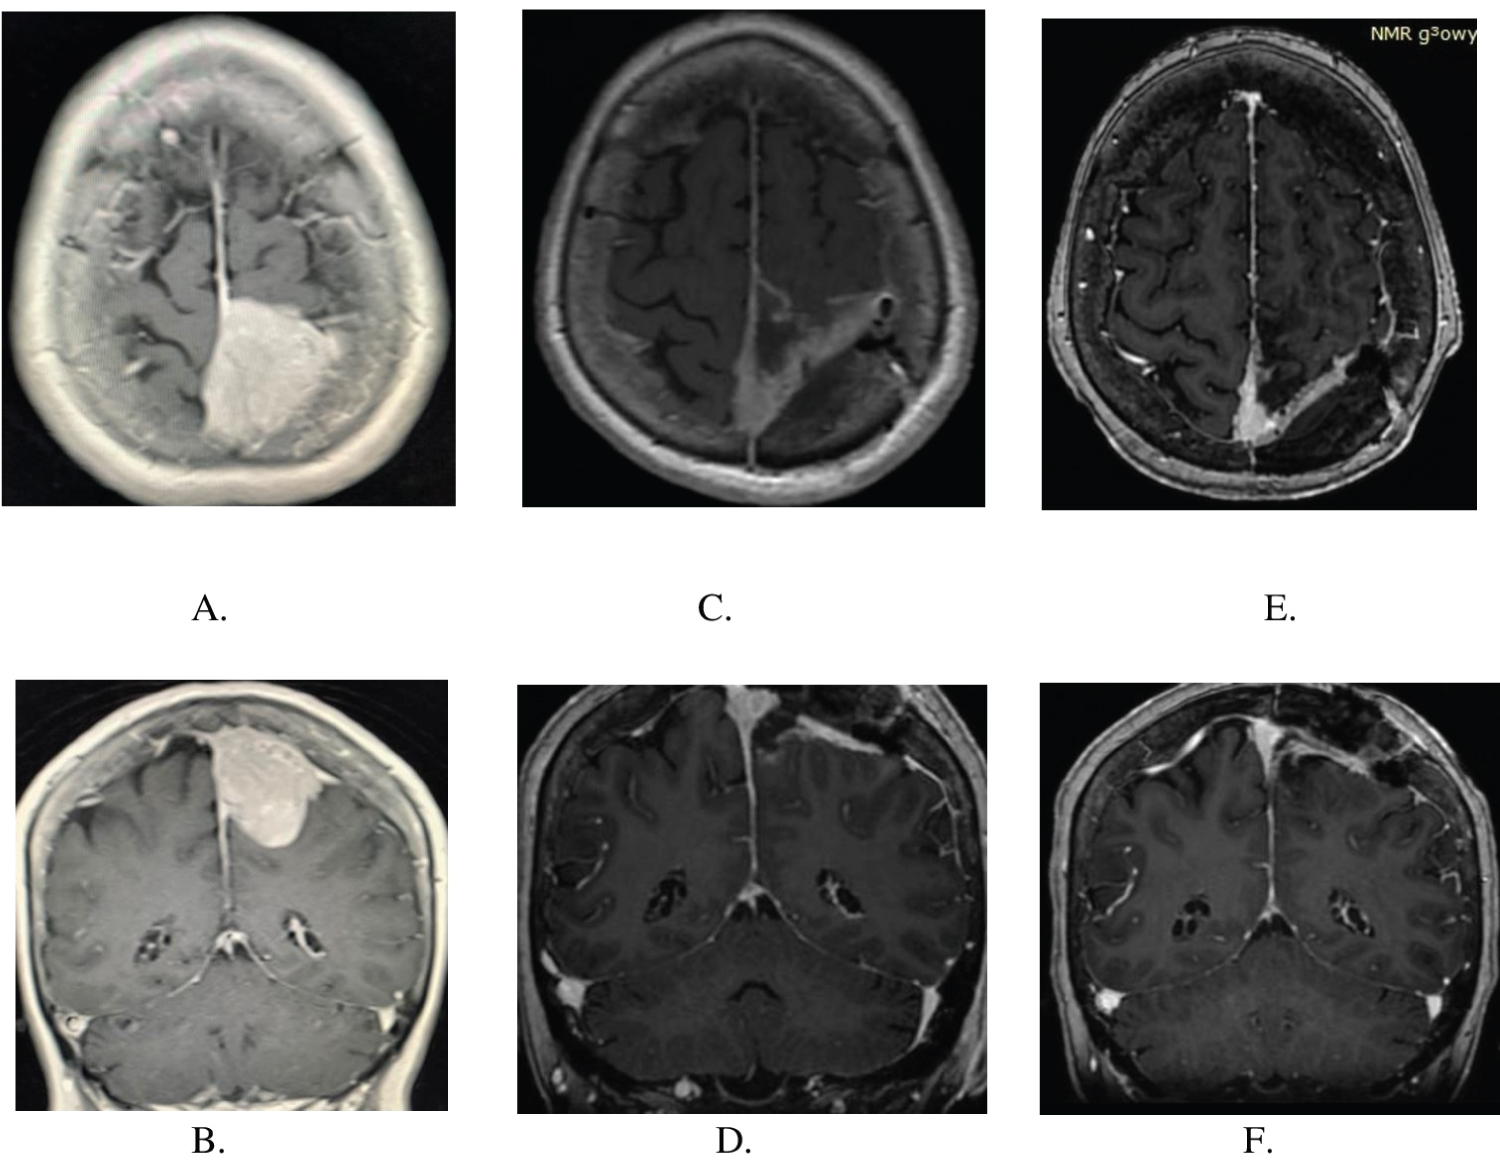

A 71-years-old non-smoking right-handed woman, presented with two months history of progressive left leg paresis. Cranial magnetic resonance imaging (MRI) revealed a 3 × 4 × 4 cm mass in the left occipital region with superior sagittal sinus infiltration (Figure 1A and Figure 1B).

Two weeks after the initial presentation, she underwent the left fronto-parietal craniotomy. Considering the superior sagittal sinus infiltration by the tumor, advanced age of the patient, a subtotal tumor resection was undertaken. Small tumor remnants within the sinus cavity were coagulated thoroughly. The infiltration of the arachnoid by the tumor increased the cerebral cortex injury. Left lower limb paresis progression was observed immediately after the procedure, and it subsequently diminished during the rehabilitation. Control magnetic resonance imaging carried out one month after surgery confirmed tumor remnants within the superior sagittal sinus cavity (Figure 1C and Figure 1D). The patient was consulted by oncologist and stereotactic radiotherapy (Cyberknife) was applied to irradiate the remnants of the tumor within the superior sagittal sinus. No tumor tissue progression was observed six months after surgery (Figure 1E and Figure 1F).

Figure 1: (A,B) MRI scans showing Choroid Meningioma in axial and sagittal plane before surgery; (C,D) MRI scans showing tumor remnants in the superior sagittal sinus one month after surgery, before Gamma Knife therapy; (E,F) MRI scans six months after surgery, recently after Gamma Knife therapy. View Figure 1